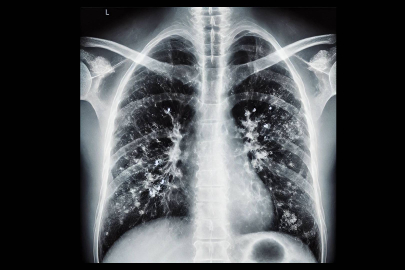

Göğüs Hastalıkları Uzmanı Prof. Dr. Tevfik Özlü, solunum yolu enfeksiyonlarının en sık görüldüğü kış aylarında, zatürre hastalığının grip ya da soğuk algınlığıyla karıştırılabileceğini ancak bazı kritik belirtilerin ayırt edici olduğunu belirterek, uyarılarda bulundu. Özlü, "Şu sıralar pek çok hasta zatürreyi fark edemiyor ve teşhiste geç kalıyor. Oysa zatürrede erken tanı çok önemli. Hekimin, 4 saat içinde doğru tedaviye başlaması, zatürreye bağlı ölümleri anlamlı şekilde azaltıyor" dedi.

Mevsimsel grip, nezle ve diğer solunum yolu enfeksiyonları genellikle hafif seyretse de bazı durumlarda zatürreye dönüşerek ciddi komplikasyonlara yol açabiliyor. Uzmanlar, zatürrenin grip ya da soğuk algınlığıyla karıştırılabileceğini fakat bazı kritik belirtilerin ayırt edici olduğunu söylüyor. Yüksek ateş, titreme, aşırı halsizlik, balgamlı ve koyu renkli öksürük, nefes darlığı ve göğüs ağrısı gibi şikayetlerin zatürre ihtimalini güçlendirdiğini belirten uzmanlar, zatürrenin özellikle yaşlılar, bebekler ve kronik hastalığı olan bireylerde ağır seyredebileceğini belirtiyor.